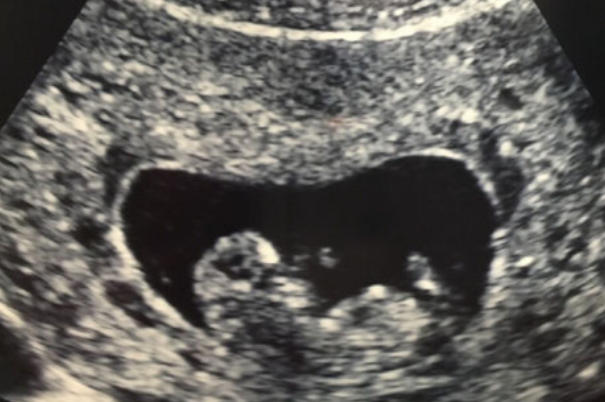

B超检查宝宝性别的理想时间通常在妊娠16至20周之间。这一时期,胎儿生殖器官已基本发育成形,B超影像能清晰显示男孩的阴茎和阴囊,或女孩的阴唇结构。过早检查可能因器官未完全分化而难以判断;过晚检查(如24周后)虽准确性高,但可能因胎儿活动频繁或母体肥胖影响影像质量。

B超检查宝宝性别的准确性受多重因素影响,包括胎儿体位、母体肥胖程度及设备精度。胎儿体位不佳(如背对探头)可能遮挡生殖器官,导致误判;母体肥胖会减弱超声波穿透力,影响影像清晰度;设备性能(如分辨率高低)也直接决定检查结果。此外,医生经验同样重要,熟练的操作者能更准确识别细微结构。